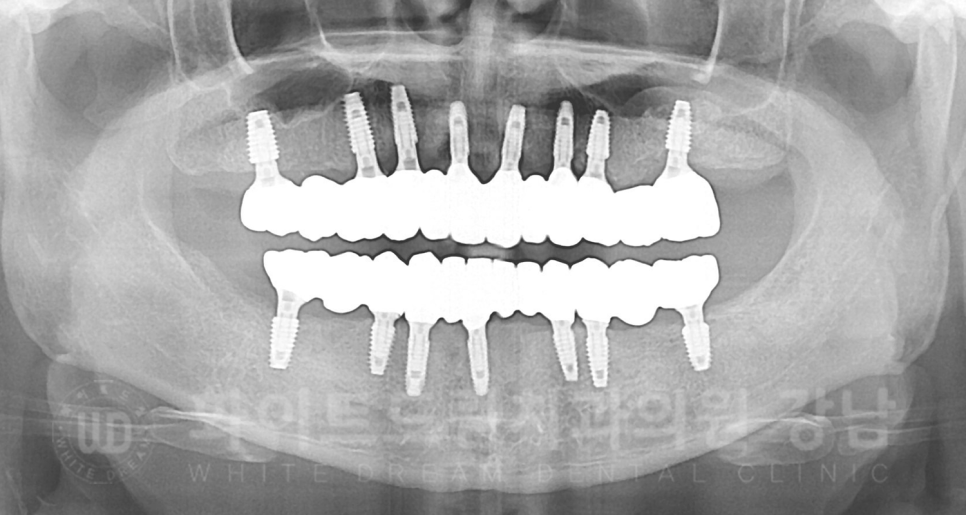

▲ 전악 식립 후 X-RAY입니다.

노란색 동그라미는 1+2차를 동시 진행한 경우이고

빨간색은 2차 수술이 필요한 상태입니다.

환자분도 초기 고정력이 좋은 임플란트는 1+2차를 동시에 진행했고,

유착기간이 필요했던 몇몇 개의 임플란트만 2차 수술을 진행하고 보철 제작에 들어갔습니다.

20.09.05 2차 수술 진행 → 20.10.17 보철 제작 시작